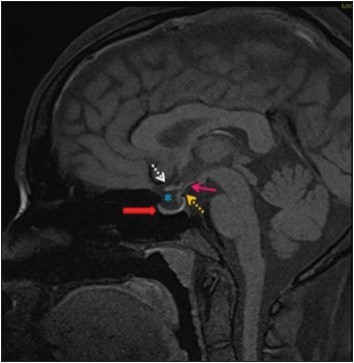

1 August 8, 2016 354 × 363 8/3/2016 AM Report – Idiopathic Intracranial Hypertension Share this: Share on X (Opens in new window) X Share on Facebook (Opens in new window) Facebook Like Loading...